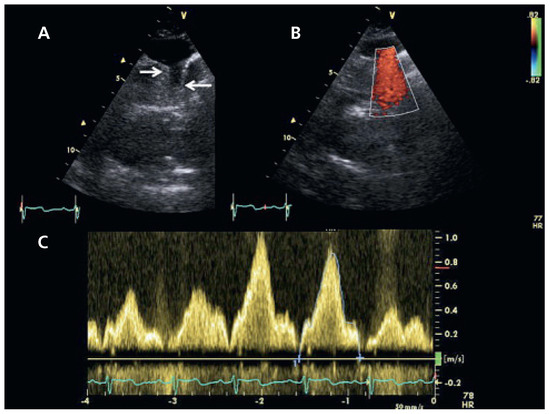

Dyspnée et Hypertension Artérielle Pulmonaire Sévère chez une Femme Âgée

by Davide Muratori, Alain Delabays and Ludovic Perrin

Cardiovasc. Med. 2011, 14(6), 182; https://doi.org/10.4414/cvm.2011.01594 - 29 Jun 2011

We describe the case of a 79-year-old female patient presenting with an exacerbated exertional dyspnoea. Clinical findings showed mild signs of right heart failure. Echocardiography detected right atrial and right ventricular dilatation, with moderate to severe PH and normal biventricular systolic function. There [...] Read more.

We describe the case of a 79-year-old female patient presenting with an exacerbated exertional dyspnoea. Clinical findings showed mild signs of right heart failure. Echocardiography detected right atrial and right ventricular dilatation, with moderate to severe PH and normal biventricular systolic function. There was no atrial septal defect. The patient was submitted to a thoracic CT scan for a suspicion of thrombo-embolic disease. To our surprise, this investigation demonstrated an isolated anomalous drainage of the left superior pulmonary vein into the left innominate vein. We attributed the pulmonary hypertension to the associated left to right shunt. Full article